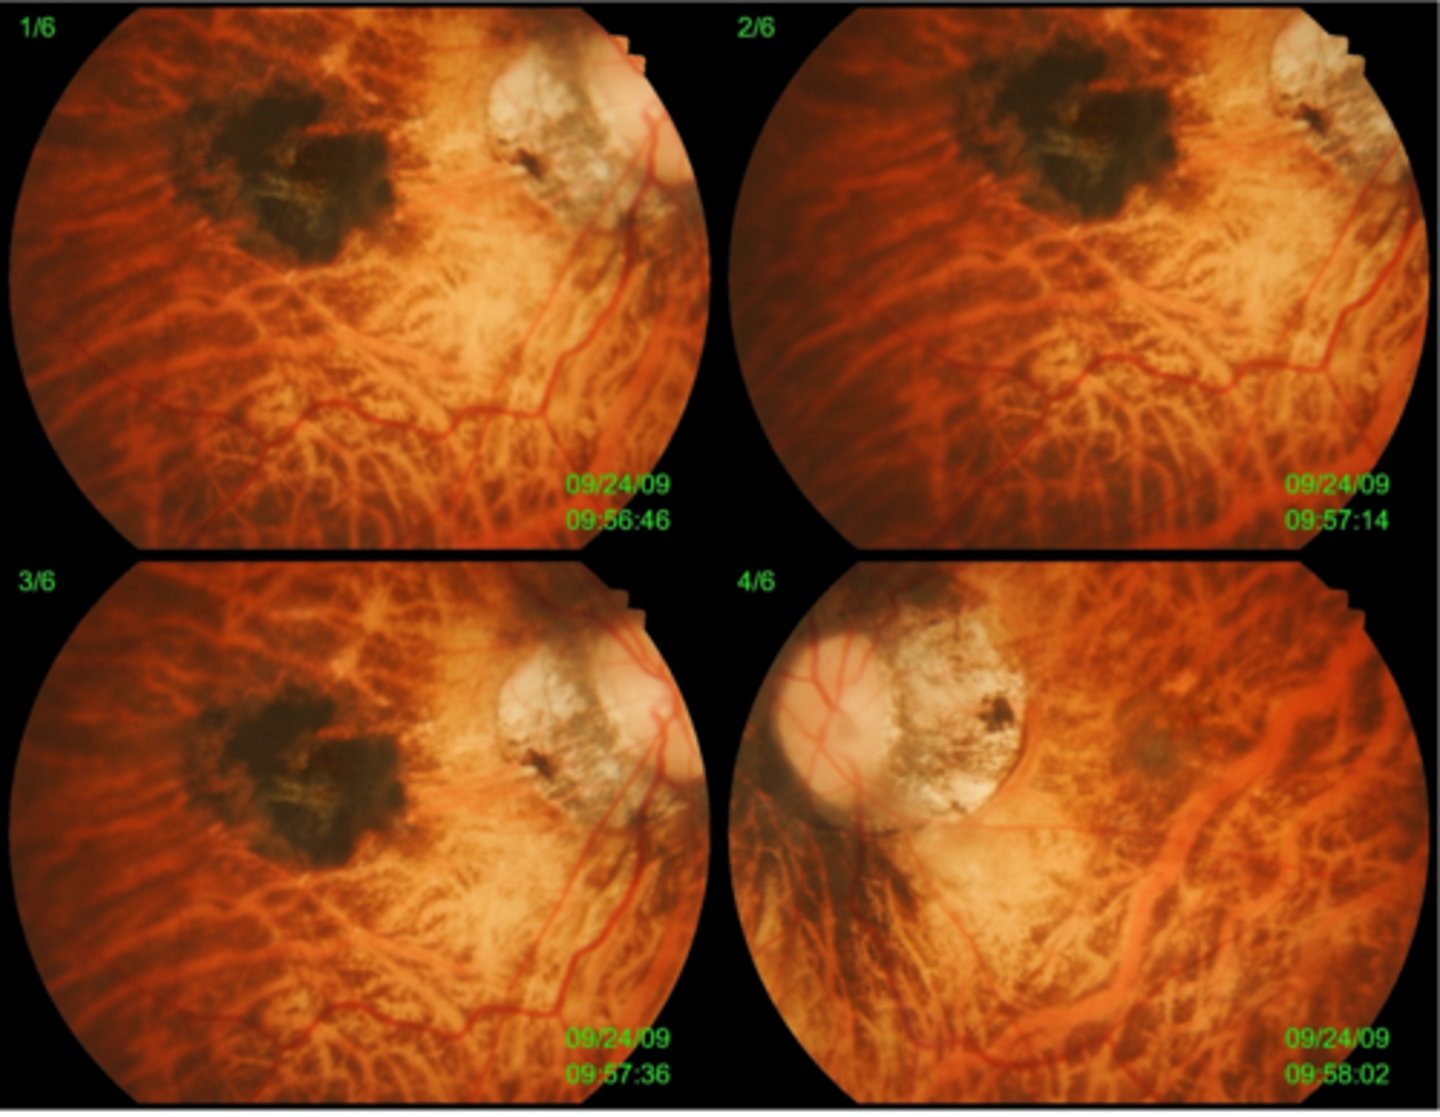

How does ocular toxocariasis appear on OCT, as seen here in patient A?

multiple light granulomas = hyperR

How does ocular toxocariasis appear on OCT, as seen here in patient B?

recurrence = granulomas with exudates, edema

How does ocular toxocariasis appear on OCT, as seen here in patient C?

granuloma now in nasal retina, fibrous memb where granuloma once was (looks like ERM)

How does ocular toxocariasis appear on B-scan here?

granuloma mass over ONH = high-reflectivity